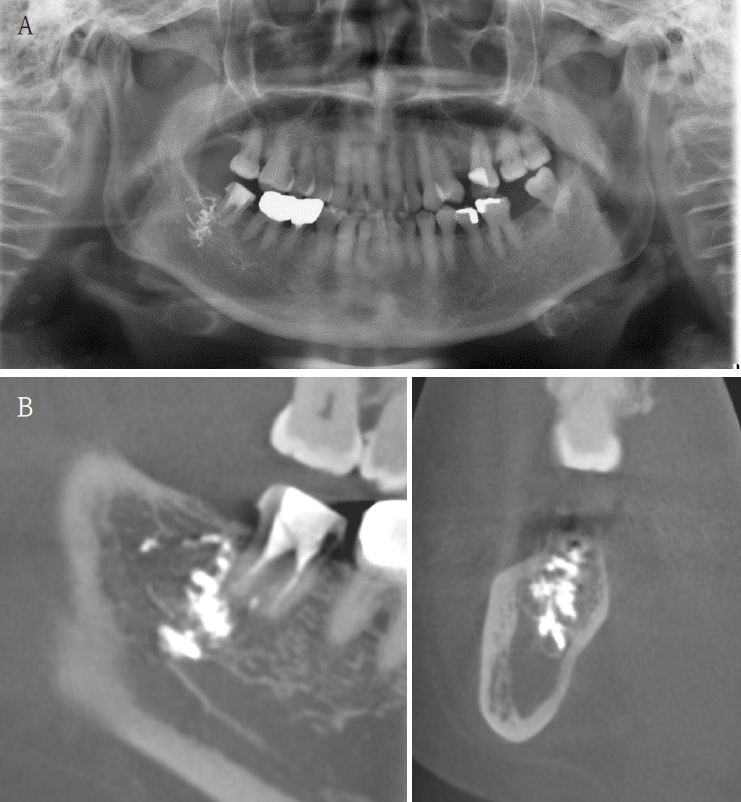

A 63-year-old female presented three days after endodontic treatment of the mandibular left second molar (#37) with symptoms of numbness in the left lower lip and gingiva. A panoramic radiograph and cone-beam computed tomography (CBCT) revealed extrusion of Calcipex II into the mandibular canal (Fig. 1). Initial neurosensory testing demonstrated mild hypoesthesia. She was admitted for foreign body removal and neurorrhaphy under general anesthesia. A post-operative panoramic radiograph confirmed the removal of the foreign body (Fig. 2). Although surgical curettage and neurorrhaphy were performed on the fourth day post-onset, no significant symptom relief was noted at the one- and two-week follow-ups. At the three-month follow-up, she reported persistent numbness with mild neuropathic discomfort but no marked improvement. A follow-up neurosensory exam is scheduled for the six-month check-up.

A. Pre-op panoramic radiograph of Case 3 patient. B. Pre-op CBCT of Case 3 patient. C. Pre-op bone scan of Case 3 patient